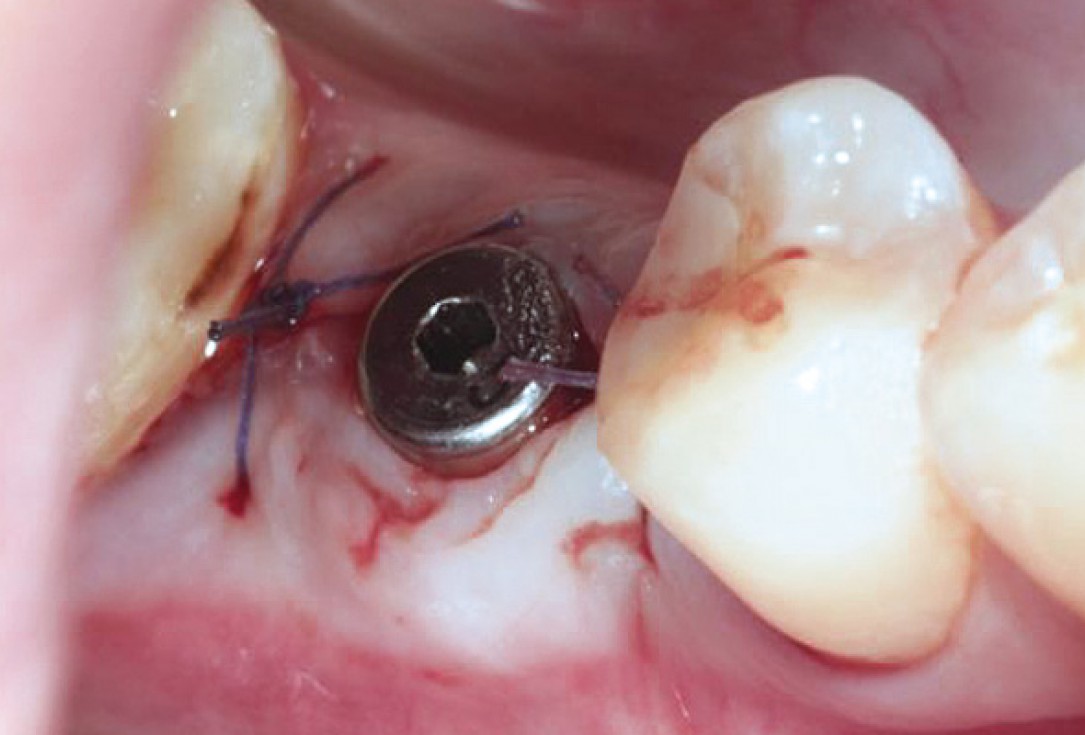

Socket preservation with permamem® - Dr. R. Rannula